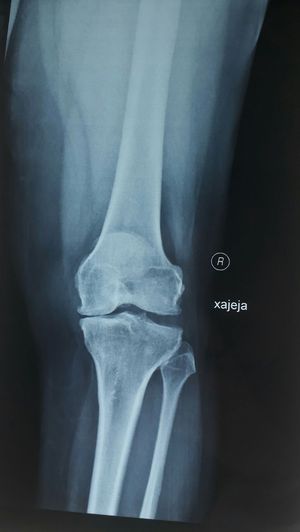

Last stage of osteoarthritis (severe osteoarthritis

Ouch! Partial knee replacement needed!